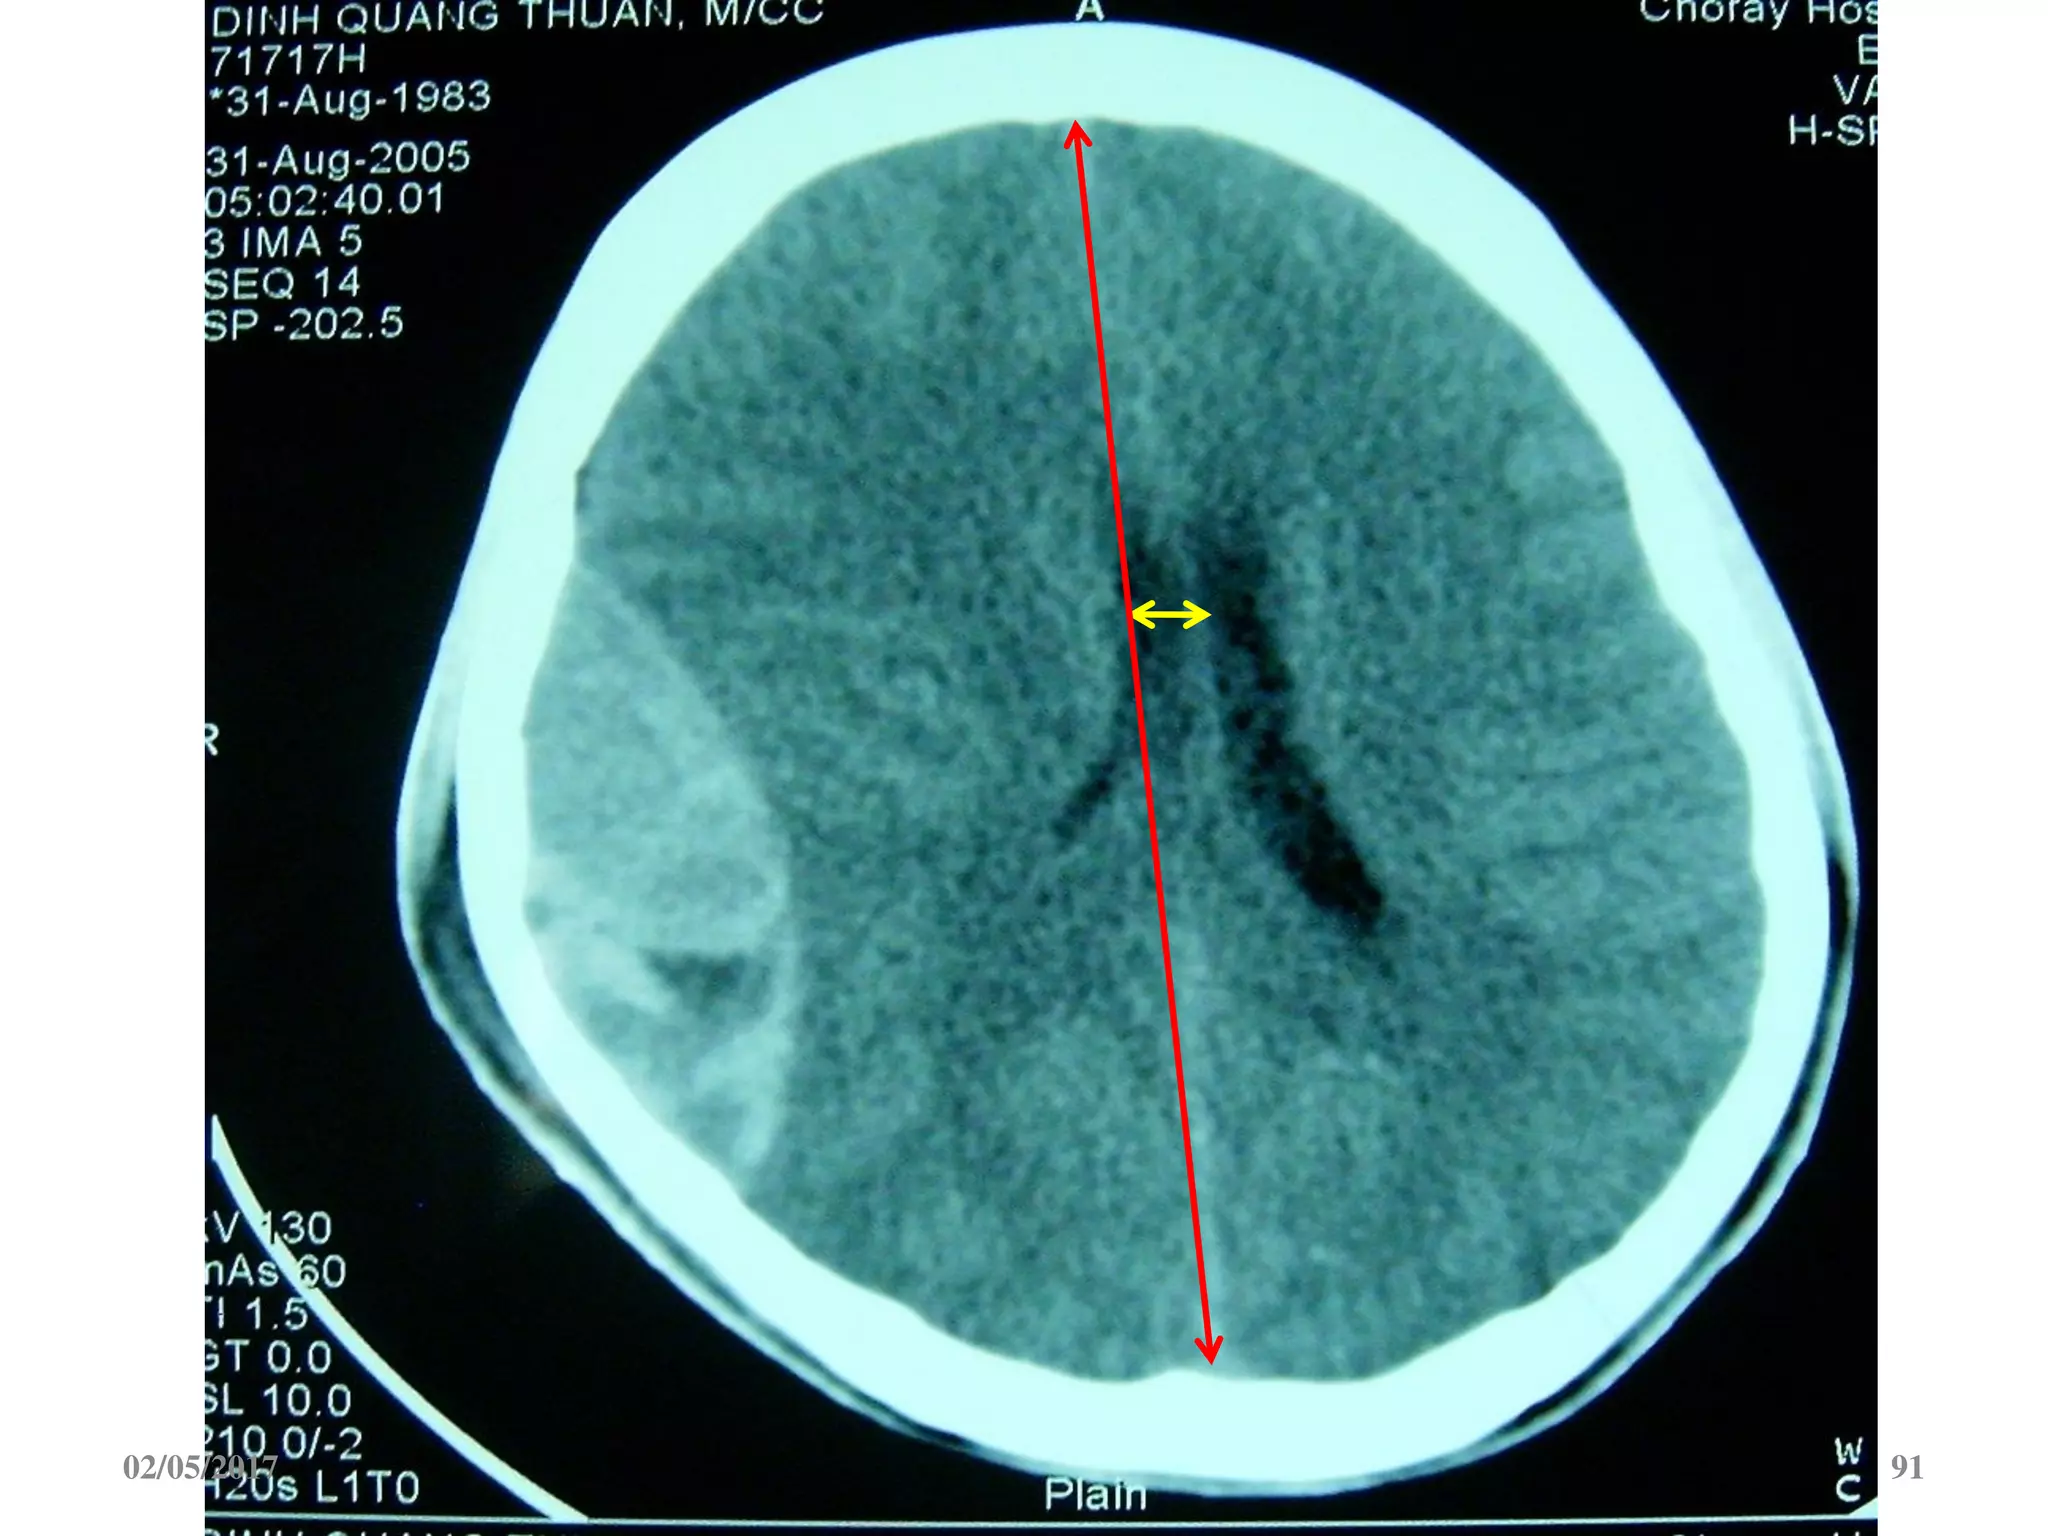

Một số chỉ định mổ

Thể tích khối máu tụ > 40 ml

 Máu tụ DMC dày > 5mm, đẩy lệch đường giữa > 5 mm

 Giãn não thất cấp

 Lún sọ hở

 Lún sọ kín hơn bề dày 1 bản sọ

Vết thương sọ não

 Máu tụ hố sau gây chèn ép não thất 4.

 Máu tụ trong não, dập não đẩy lệch đường giữa >5 mm

 Mở sọ giải áp: khi tăng áp lực nội sọ không kiểm soát

* V=a x b x c/2 (cm3)